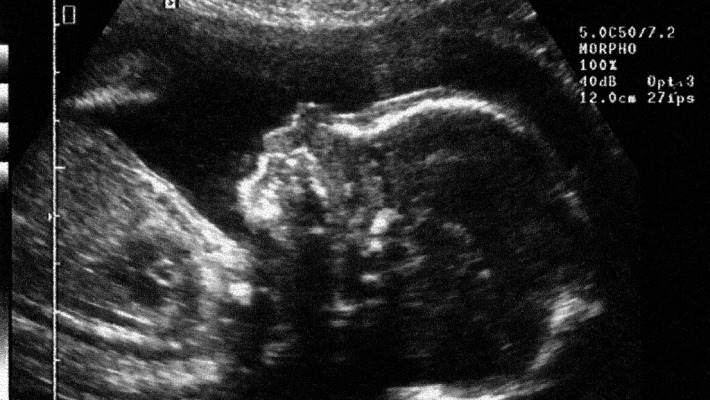

"Une équipe de médecins Hong Kong a eu la surprise de découvrir à l'intérieur du corps d'une petite fille qui venait de naître une paire de "fœtus" ou tumeurs partiellement formés. Un phénomène extrêmement rare. "